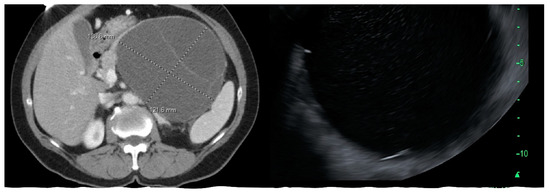

MCN, SCA, and SPN are solitary cysts. MCN and SCA lack communication with the main pancreatic duct and do not show pancreatic duct dilation on imaging. IPMN, by definition, demonstrate communication with the pancreatic duct, have the dilation of the duct, and are commonly multiple. IPMNs are more common in the head and neck region but can be found in other locations (Figure 2). They can be multifocal and should be considered along with pseudocysts when multiple cysts occur in the pancreas. MCNs are exclusively seen in the body or tail of the pancreas (Figure 3). While SCA can occur in the head, most SCA are located in the body or tail (~70–75%). There is no specific location of SPN (Table 1).

Figure 3.

CT scan and endoscopic ultrasound images of mucinous cystic neoplasm in the body and tail of pancreas.